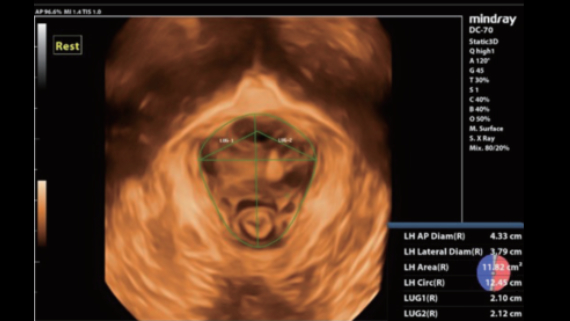

Imagens clĂnicas